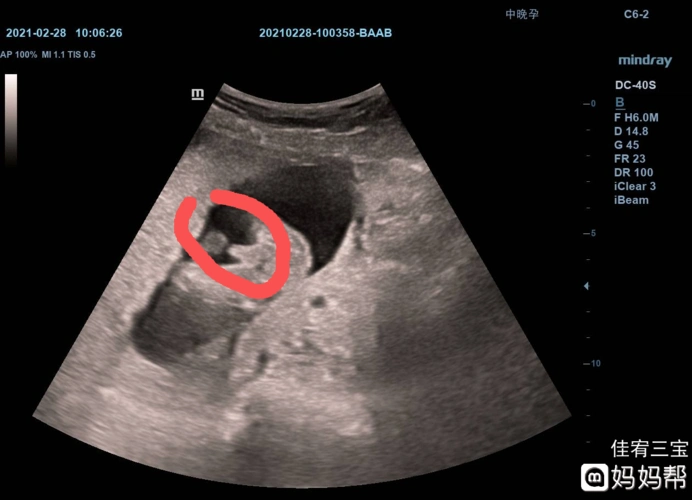

医生说怀男孩的特点